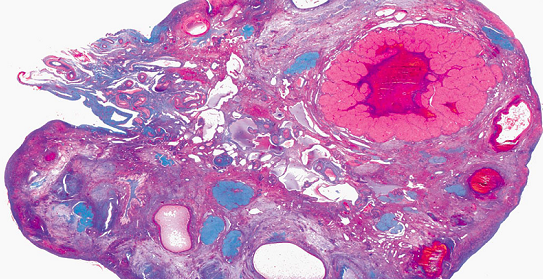

研究人员们使用3D打印机打印出了一个生物支架来支持产生激素的细胞和成熟的卵细胞(即卵母细胞)。这种生物支架是用明胶(一种来源于动物胶原蛋白的生物材料)支撑的。科学家们在在制造该支架时采用了生物学原理,该支架既要有足够的刚性以便于在手术过程中的操作,又要为提供足够的空间支持卵母细胞生长、血管形成和排卵。在使用人体细胞培养时,研究人员们确定了最佳的支架设计应该纵横交错,这样可以通过多点固定住细胞。该支架是用卵泡借种以生成生物假体的,所谓的卵泡是一个球形的组织,中间是卵母细胞,周围围着生成激素的细胞。

为了测试该植入物,研究人员移除了实验小鼠的卵巢,并用卵巢生物假体取而代之。在此之后,小鼠排卵,生下健康的幼崽,并且能够养护幼崽。

科学家们称,植入的支架结构支撑了小鼠体内血管的生长,他们没有使用任何物质以刺激该过程。利用一种灵感来自于人类生物学的制造技术,研究人员开发出了一种可以与人体组织相互作用的支架。这一技术有可能在未来更加复杂的软组织替换中发挥作用,Laronda说。